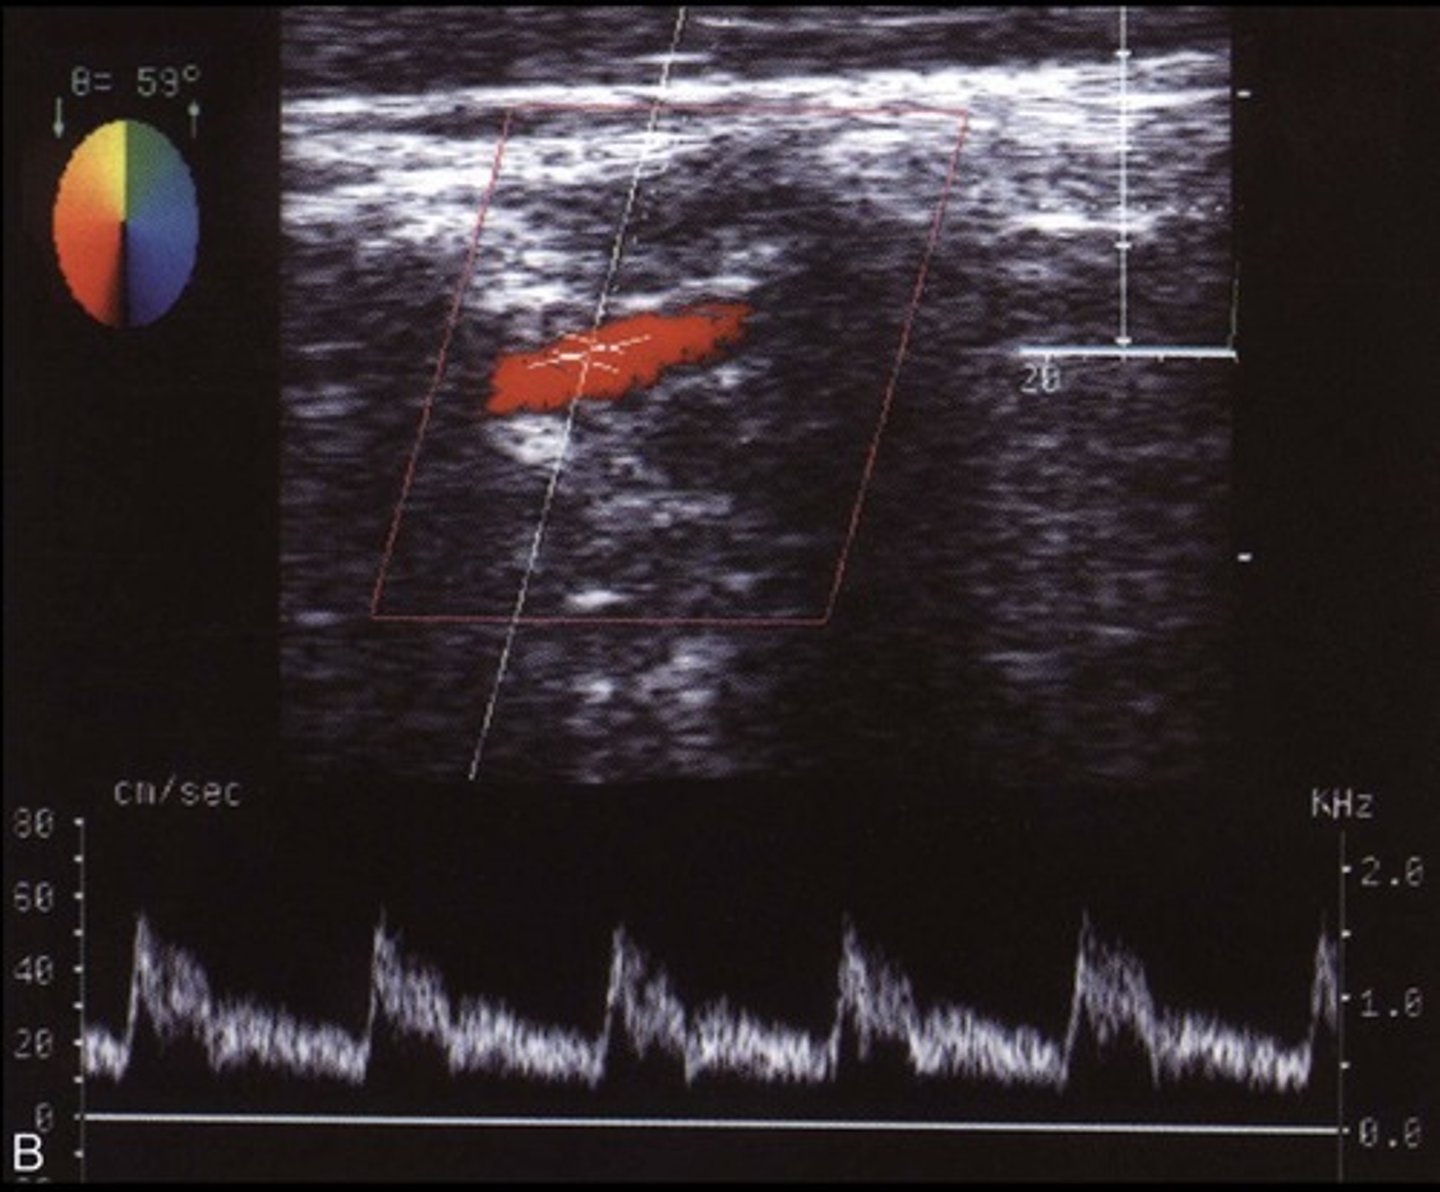

Normal Vertebral A Waveform